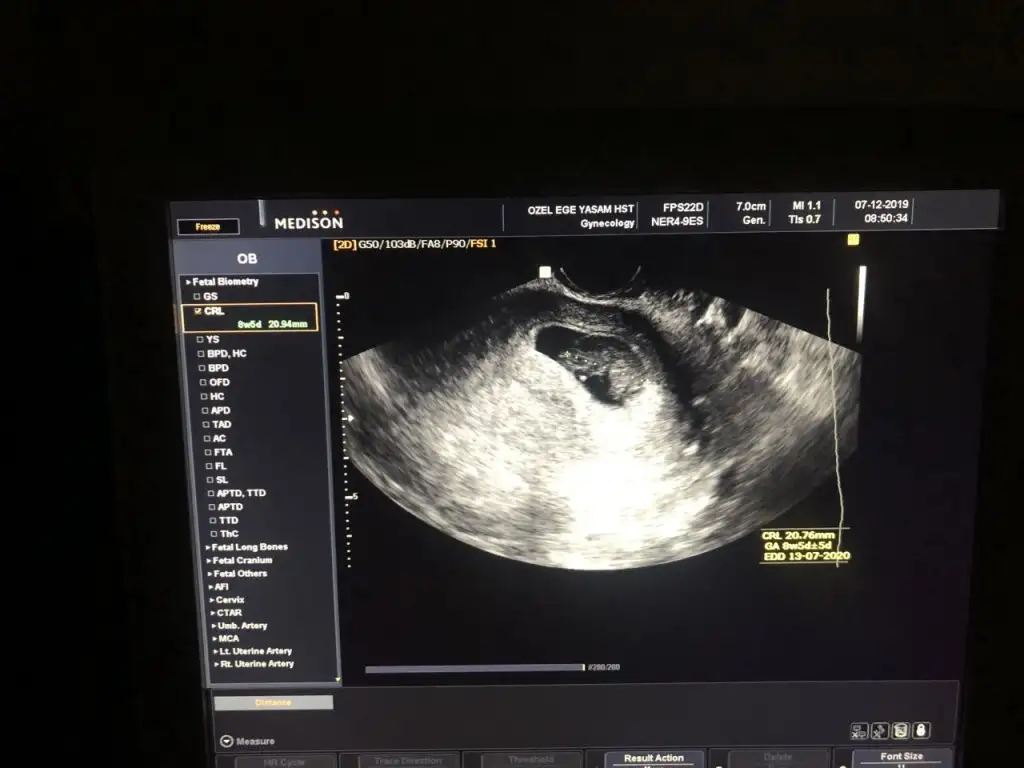

9 haftalıktı burdabi de benim minnoşuma bakar mısınız

11 yada 12 hafta olmalıbi de benim minnoşuma bakar mısınız vajinal muayane 9 haftalık burda